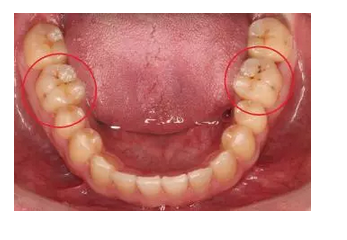

牙齒出現(xiàn)的齲壞,從外面看就表現(xiàn)為一個(gè)黑點(diǎn),通常位于窩溝點(diǎn)隙(牙面上點(diǎn)狀或線狀凹陷)。齲齒的罪魁禍?zhǔn)资强谇恢械哪承┘?xì)菌,但它們破壞牙齒也是需要時(shí)間的,從初期的變色到最終形成齲洞,通常需要1年半到2年。在此期間,我們多留心自己的牙齒,完全可能把齲壞扼殺在萌芽階段。如何才能及時(shí)發(fā)現(xiàn)這種隱匿的蛀牙呢?找位好牙醫(yī),半年檢查牙齒!

一旦確認(rèn)牙齒上的小黑點(diǎn)是齲齒就應(yīng)該盡早修補(bǔ),以阻止病變的發(fā)展。如果任由其繼續(xù)發(fā)展就會(huì)變成明顯的齲洞,這時(shí)患者會(huì)對(duì)冷熱酸甜等食物刺激敏感;當(dāng)損傷進(jìn)一步到達(dá)牙髓(即老百姓說的“牙神經(jīng)”),就會(huì)疼痛難忍,嚴(yán)重影響日常生活。

很多人都會(huì)等到牙痛得受不了,才到醫(yī)院就診。這時(shí)通常不能靠單純補(bǔ)牙來解決問題,可能還要做根管治療甚至拔除患牙、進(jìn)行假牙修復(fù),費(fèi)時(shí)費(fèi)力又費(fèi)錢,人還遭罪,可謂"小洞不補(bǔ),大洞吃苦”。